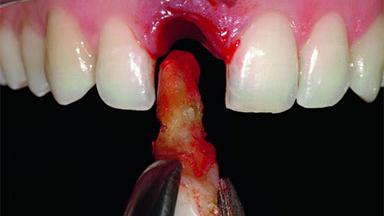

Replacement of an Upper Right Central Incisor with Root Resorption: Ridge Preservation, Delayed Placement of an NC Bone Level Roxolid Implant

A 32-year-old female Caucasian patient with a compromised maxillary right central incisor was referred to us by a general dentist. Her chief complaints were discomfort and mobility of tooth 11 with unsatisfactory esthetics due to discoloration. The patient reported a previous trauma, some years earlier, as the origin of pathology on the afflicted tooth. Anamnesis was negative for any other dental or periodontal pathology in the remaining dentition. The patient did not take any medication and reported to be a light smoker (5–10 cigs/day). She had high esthetic expectations of her treatment. The extraoral examination revealed a high smile line with full exposure of her maxillary teeth and surrounding soft tissue in the area between the second premolars.